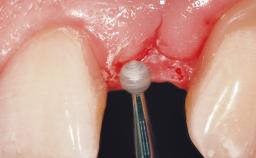

Placement Protocol Immediate implant placement

Socket Morphology Single-root socket

Socket Integrity Sufficient, with intact bone walls

Bone Volume Sufficient, with intact walls